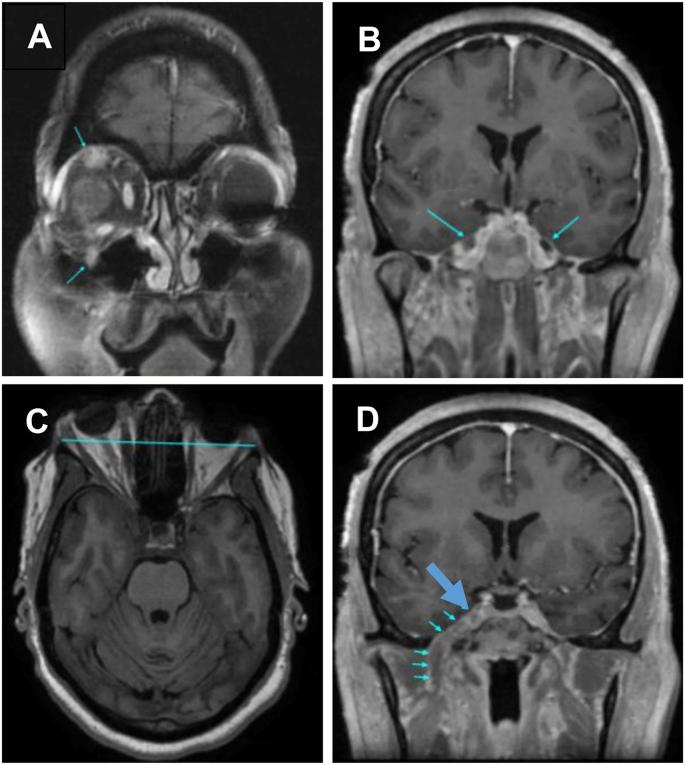

A 57-year-old African-American woman presented with a 4-year history of right eye proptosis with tearing, headaches, and worsening right-sided trigeminal neuralgia symptoms and jaw pain. HIV and diabetes tests were negative and thyroid function was normal. MRI identified abnormal thickening of all trigeminal nerve divisions and proptosis secondary to right trigeminal nerve V1 division enlargement. The excised tissue contained S-100 positive Schwann cells in an onion-bulb pattern. Headaches resolved, but proptosis and mild trigeminal neuralgia remained 1 year post-surgery.

Trigeminal HIN is very rare, but presents as chronic progressive ocular symptoms with trigeminal neuralgia. Trigeminal nerve hypertrophy is identified by MRI and confirmed histopathologically by detection of Schwann cells in an onion bulb formation.